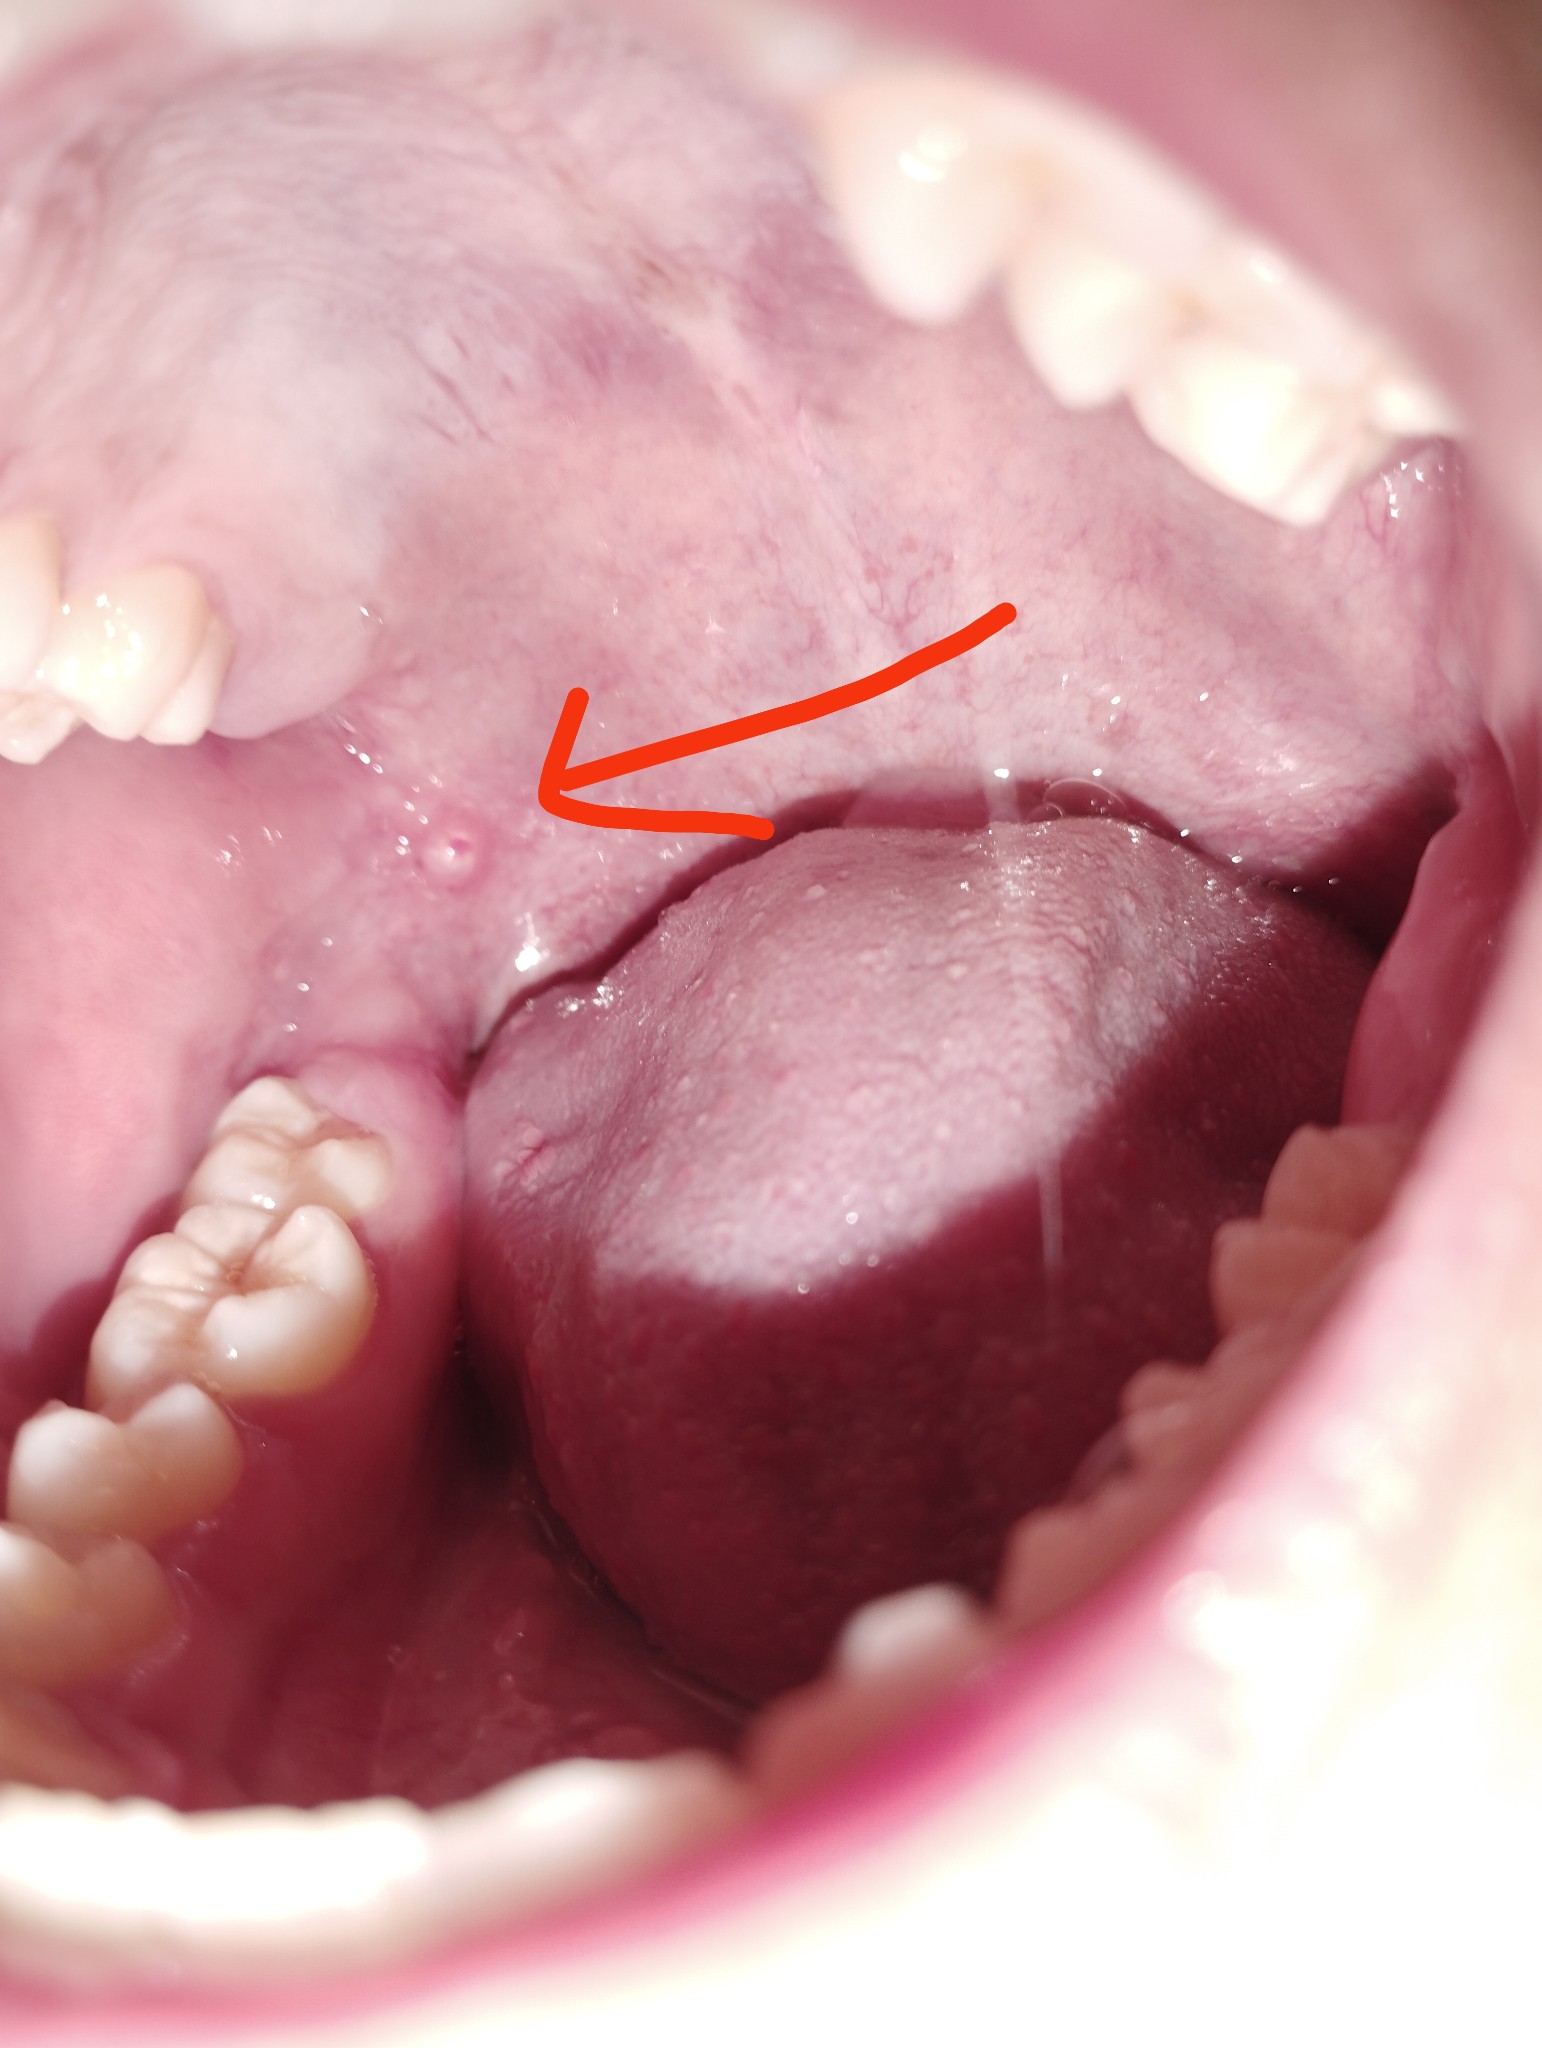

มันคืออะไรหรอครับมันเป็นเหมือนก้อนวงกลมใสๆนิ่มๆพอลิ้นไปโดนก็ไม่รู้สึกเจ็บ